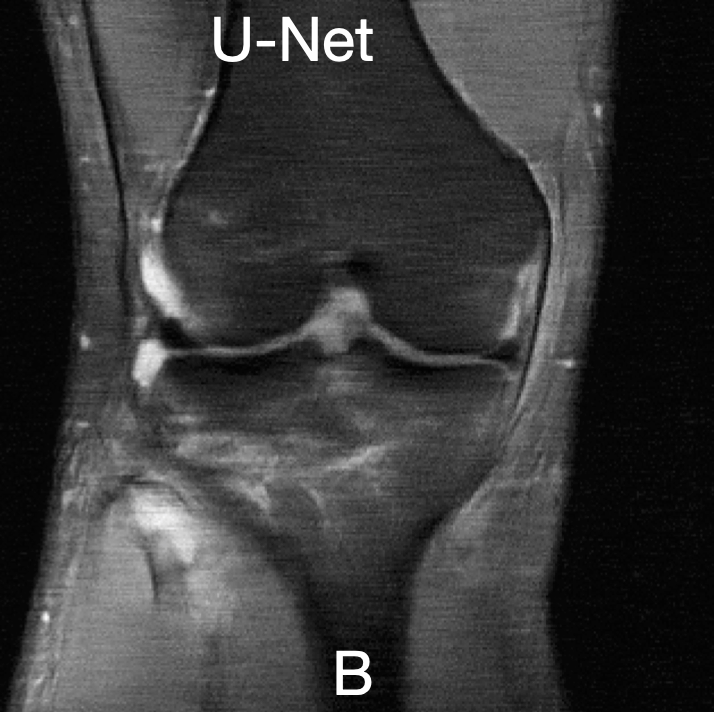

For a qualitative assessment of the results, we show some examples in figure˜0.B.1 for the UNet model and figure˜0.B.2 for the E2E-VarNet model of reconstructions where the attack was successful. These figures are structured as 2x2 panels of images where the first row displays the original and perturbed input samples and the second row displays the corresponding model-based reconstructions. Areas which we believe contain hallucinatory structures are highlighted in red.

We notice from LABEL:fig:unet-best1 and LABEL:fig:unet-best2 that the multi-coil images seem to be more vulnerable than the single-coil ones, in the sense that the resulting distortions are more severe for multi-coil data. The generated perturbations also seem easier to spot for single-coil data. This may be explained by the fact that perturbations in the multi-coil images can be more “spread out” across the coils, whereas with single-coil data this is not possible. This is consistent with the observation that vulnerability to adversarial examples increases with data dimensionality [14, 27]. Although we cannot compare to single-coil data for the E2E-VarNet, we do notice large distortions in LABEL:fig:varnet-best1 as well that go far beyond the boundaries of our inserted detail. On the multi-coil brain data, the hallucinations seem less severe for both models compared to the knee data, but the distortions can still be significant as they tend to resemble non-existent sulci. For knee images, the distortions appear to substantially change the structure of the knee joint, especially on multi-coil data.

We conclude that the adversarially perturbed samples can lead to realistic reconstructions which exhibit biologically plausible distortions that could mislead expert interpretation, and that the insertion of the artificial detail will often cause further distortion beyond the original target region. For both models, this is especially apparent in the multicoil knee data, where the shape of the knee joint tends to change significantly when the detail is inserted.